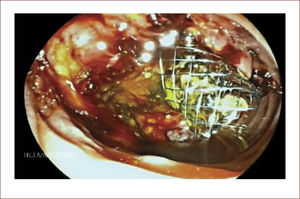

En la actualidad existen los AXIOS (que son la solución al problema): stents que se aplican entre el estómago o duodeno y el quiste y quedan anclados como un botón, a través del cual el endoscopio puede entrar y realizar el lavado directo de las secreciones y detritus26Figura 6.

Hemos tenido éxito en la mayoría de pacientes, pero también hemos tenido complicaciones. En cuatro años llevamos 11 pacientes manejados y dos complicaciones. En una de las pacientes se presentó un neumoperitoneo, que se manejó en forma conservadora y la paciente evolucionó satisfactoriamente, con resolución del quiste a los dos meses. Otra paciente presentó un sangrado intra quístico y ruptura del quiste por el sangrado, luego fue operada y manejada desde ahí por el grupo quirúrgico. Su evolución fue tórpida por complicaciones no derivadas del drenaje del quiste. Figura 7.